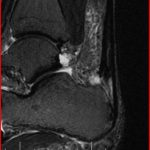

- NMR beeld ernstige ontsteking en partiële scheur middendeel achillespees bij 35j loper

- NMR beeld van ernstige ontsteking en scheur in onderste deel achillespees

- NMR beeld ernstige ontsteking middendeel patellapees bij 37j judoka

- NMR beeld ernstige ontsteking en scheur onderste deel patellapees bij 37j judoka

- NMR beeld van ernstige inflammatie bovendeel patellapees (Apexitis Patellae of Jumper’s Knee)